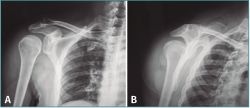

A la exploración física presenta dolor intenso a la palpación e impotencia funcional en el hombro, sin deformidad evidente y con bloqueo de los movimientos rotacionales. Tras realizar radiografías simples en proyecciones anteroposterior e “Y” de escápula (Figura 1), se diagnostica de luxación posterior de hombro.

Figura 1. Radiografía anteroposterior (AP) (A) y proyección en “Y” de escápula (B) donde se objetiva una luxación glenohumeral posterior. En la proyección AP podemos apreciar el clásico signo de la bombilla (light-bulb sign) debido a la rotación interna del brazo.